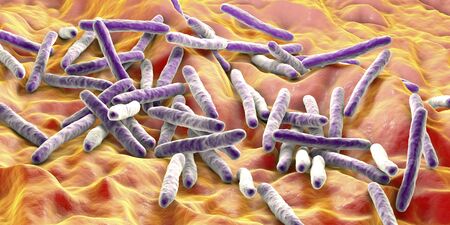

A highly detailed microscopic view of bacteria, representing microbiology, infections, science, biotechnology, disease research, and microbial life in healthcare

Bacteria Bacillus anthracis, the causative agent of anthrax disease, 3D illustration

Bacteria Mycobacterium tuberculosis

Bacteria Mycobacterium tuberculosis, the causative agent of tuberculosis, 3D illustration, can be used for M. leprae, M. avium complex and other mycobacteria